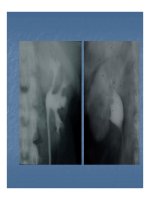

Sái niÖu qu¶n tr¸i

Cacci - Ricchi